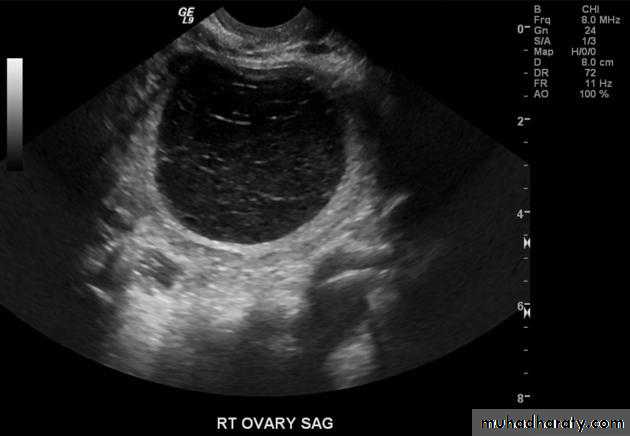

Ovarian cysts

Ovarian cysts are commonly encountered in gynecological imaging, and vary widely in etiology, from physiologic, to complex benign, to neoplastic.Small cystic ovarian structures should be considered normal ovarian follicles unless the patient is pre-pubertal, post-menopausal, pregnant, or the mean diameter is >3.0 cm

Radiographic features

Ultrasound is usually the first imaging modality for assessment of ovarian lesions. Simple ovarian follicular cysts are:

anechoic

intraovarian or exophytic;

have an imperceptible wall